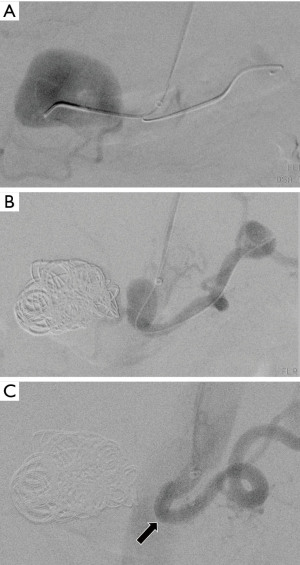

Hepatic artery aneurysms are the second most common type, accounting for approximately 20% of VAAs (Figure 2). For aneurysms affecting the proper hepatic artery, the recommended treatment involves the use of covered stents, including flow-diverting stents or stent-assisted coil embolization (Figure 3). This technique helps preserve hepatic artery blood flow and minimizes the risk of severe organ ischemia. Occlusion of the proper hepatic artery through coil embolization can result in hepatic infarction, despite the liver’s dual blood supply and portal vein patency. On the other hand, in cases involving the common hepatic artery, coil embolization can be safely performed if collateral flow to the proper hepatic artery is secured via the gastroduodenal artery (51). For these particular instances, simultaneously implanting a covered stent from the celiac trunk to the splenic artery may be beneficial in occluding the inflow to the common hepatic artery (Figure 4). Embolization of intrahepatic branches using coils is typically carried out without complications, due to the extensive intraparenchymal anastomotic arterial network.